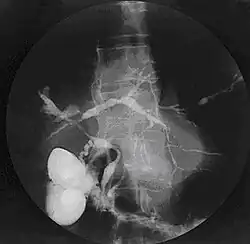

Cholangiogram of primary sclerosing cholangitis

Historically, a cholangiogram would be obtained via endoscopic retrograde cholangiopancreatography (ERCP), which typically reveals "beading" (alternating strictures and dilation) of the bile ducts inside and/or outside the liver. Currently, the preferred option for diagnostic cholangiography, given its noninvasive yet highly accurate nature, is magnetic resonance cholangiopancreatography (MRCP), a magnetic resonance imaging technique. MRCP has unique strengths, including high spatial resolution, and can even be used to visualize the biliary tract of small animal models of PSC.[22]